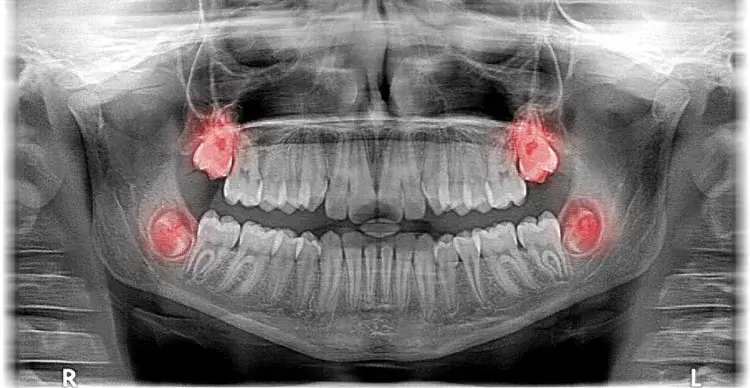

Czy ósemki rosną na górze? Odkryj prawdę o zębach mądrości

Czy ósemki rosną na górze? Dowiedz się, gdzie wyrastają zęby mądrości i jakie mogą wystąpić problemy podczas ich pojawiania się.